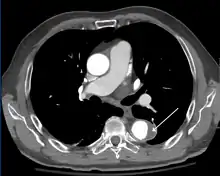

MRI

MRI of an aortic dissection

1. Aorta descendens with dissection

2. Aorta isthmus

Magnetic resonance imaging (MRI) is also used for the detection and assessment of aortic dissection, with a sensitivity of 98% and a specificity of 98%. An MRI examination of the aorta produces a three-dimensional reconstruction of the aorta, allowing the physician to determine the location of the intimal tear and the involvement of branch vessels, and to locate any secondary tears. It is a noninvasive test, does not require the use of iodinated contrast material, and can detect and quantitate the degree of aortic insufficiency.

The disadvantage of the MRI scan in the face of aortic dissection is that it may be available only in larger hospitals, and the scan is relatively time-consuming, which could be dangerous in people who are already very unwell. Due to the high-intensity magnetic fields used during MRI, it cannot be used on individuals with metallic implants. In addition, some individuals experience claustrophobia while surrounded by the MRI magnet.